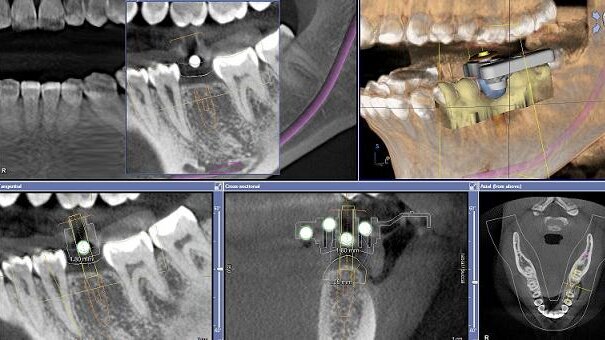

The patient was scanned using the CEREC Bluecam and a proposal for the missing tooth was created. A collimated CBCT scan of the lower jaw was taken using GALILEOS (Sirona) with a CEREC Guide reference body set in thermoplastic over the edentulous area.

The reference body is identified by the software and a virtual implant placement along with the CEREC crown proposal is imported into the software. This allows the clinician to place the implant virtually, with reference to the ideal final crown position. In this case, it was deemed that a screw-retained restoration would be desirable; hence, the screw-access hole was positioned through the centre of the crown.

Once the implant position had been decided, the information was ported to the CEREC software and using a CEREC Guide Bloc a drill body was milled by the CEREC MC XL milling machine. Once this has been milled, it will lock tightly into the thermoplastic drilling template. At this point, the surgical guide is complete and can be used on the patient.